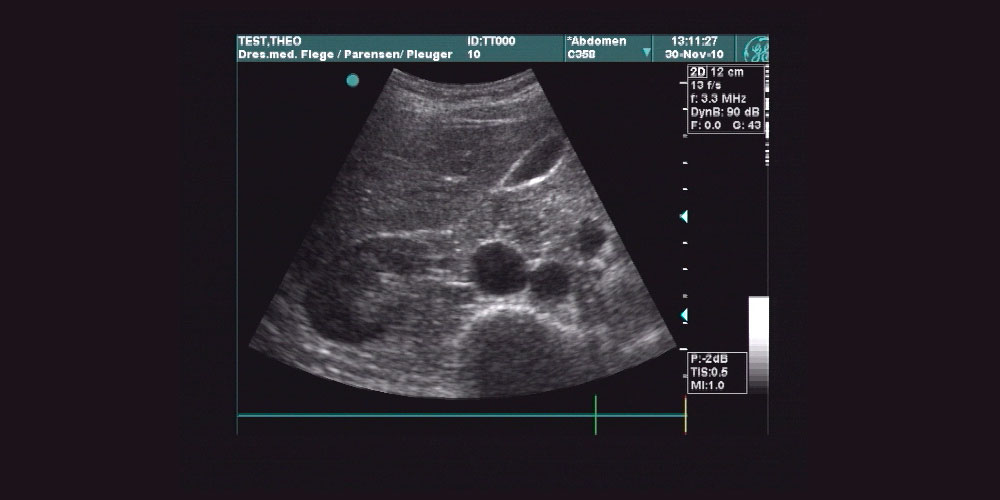

Die Sonographie ist eine Untersuchungs­methode mittels Ultraschall zur Beurteilung z. B.

Bauchorgane (Leber, Nieren, Bauchspeicheldrüse, Bauchgefäße etc.)